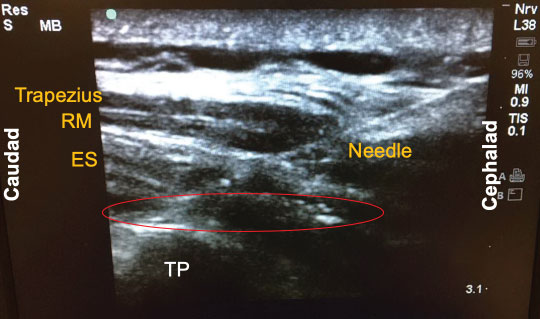

Since its introduction a few years ago, there have been numerous descriptions published on how to perform the ESP block. The following is a brief summary of the technique used to perform the block on our previously-described patient. With the patient in the sitting position, a high-frequency linear ultrasound probe was placed longitudinally on the patient's back approximately 3 cm lateral to the 5th thoracic (T5) spinous process. Three muscles above the hyperechoic transverse process were identified: trapezius, rhomboid major, and erector spinae in order of superficial to deep layers (Figure 1). A 10-cm 18-gauge Tuohy needle was inserted in-plane with the ultrasound beam at a 30° angle in a cephalad to caudal fashion. The tip of the needle was directed to the myofascial plane between the erector spinae muscle and the T5 transverse process (Figure 2). Following negative aspiration of blood, 20 mL of 0.25% ropivacaine was incrementally injected. Linear fluid spread deep to the erector spinae muscle was visualized in real-time. Finally, for continuous postoperative infusion, a 20-gauge catheter was threaded through the Tuohy needle and secured at the skin with a goal of having 5 cm of catheter left in the myofascial plane.

Figure 2: Local injection into the erector spinae (ES) plane. The tip of the needle (red circle) was directed to the myofascial plane between the erector spinae muscle and the T5 transverse process (TP). RM: Rhomboid Major.